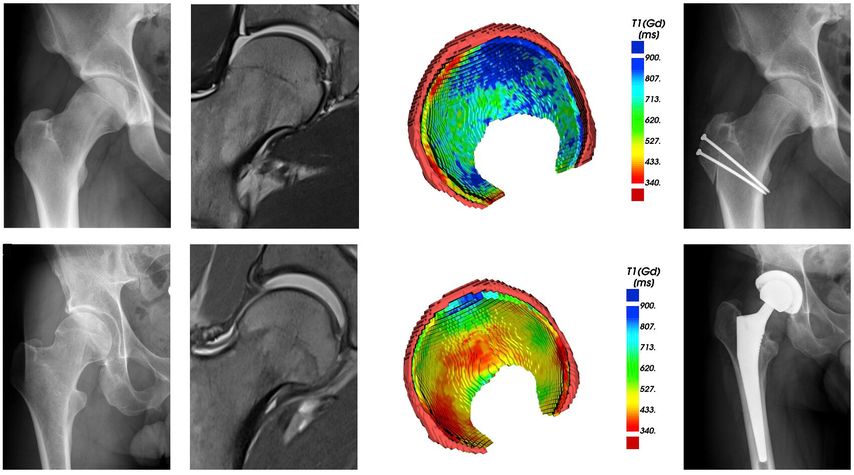

Fig. 1: Traction MR arthrography allows for better visualization of the opposing acetabular and

To improve visualization of the central joint cavity during MR arthrography, axial leg traction can be applied, similar to the joint distraction needed during hip arthroscopy (Fig. 1). Traction MR arthrography of the hip has shown high accuracy in detecting chondrolabral lesions, ligamentum teres injuries, and intra-articular loose bodies and has demonstrated its value in predicting failure of FAI surgery.5–8 It is particularly helpful for better visualizing the extent of cartilage damage in older patients with mild radiographic joint degeneration and thus aid in surgical decision making. Traction MR arthrography can also detect unstable labral tears in patients with hip dysplasia and may aid in planning treatment for femoral head necrosis in young patients with early collapse and preserved joint space.4